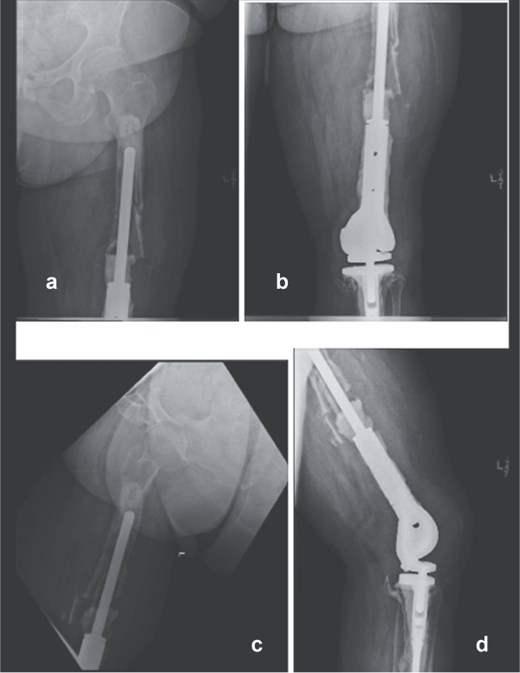

A 61-year-old woman with a history of osteosarcoma treated with DFR who presented with recurrent infection, extensor mechanism loss, and progressive proximal femoral bone loss. She had undergone multiple failed revisions and debridements. Radiographs showed loosening of the proximal femoral stem with minimal remaining viable femoral bone (Fig. 1). Given the extent of bone loss and infection, a two-stage revision with TFR was planned.

Preoperative anteroposterior (a and b) and lateral radiographs (c and d) of the right femur showing loosening of the proximal femoral stem and extensive proximal femoral bone loss following multiple distal femoral replacement revisions for osteosarcoma.